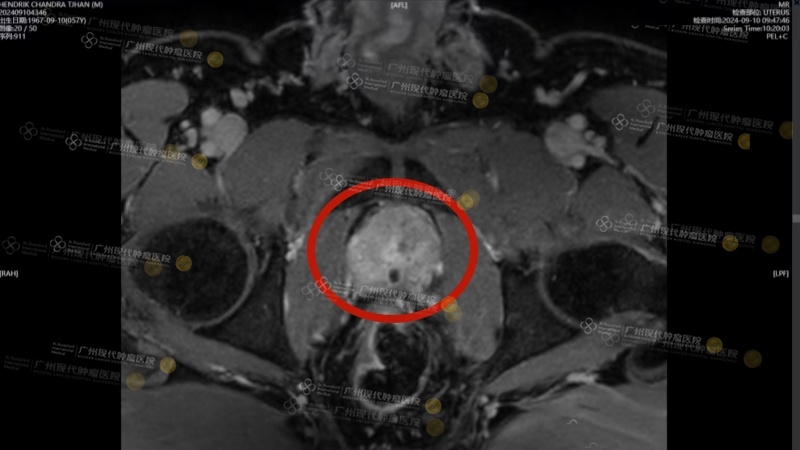

Kết quả MRI cho thấy trong tuyến tiền liệt có một khối choán chỗ kích thước 2.6x3x2cm. Kết quả giải phẫu bệnh xác định là ung thư biểu mô tuyến, với điểm Gleason 7.

Sau điều trị xâm lấn tối thiểu, khối u tuyến tiền liệt khoảng 3 cm gần như “biến mất hoàn toàn”.